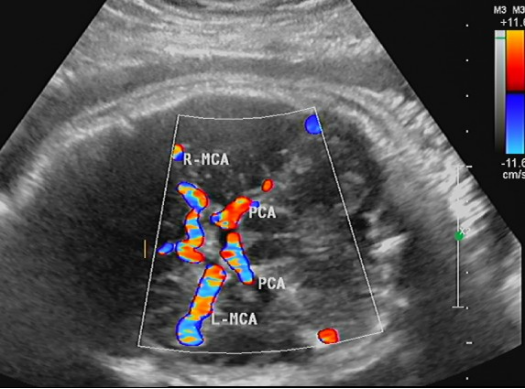

经颅彩色多普勒超声,也称TCCD/TCCS,这是一项无创、价格低廉、重复性强的检查手段,TCCD在TCD成像基础上,加入二锥灰阶成像及彩色多普勒血流成像,可直观地识别颅内结构,更准确地定位颅内血管,通过角度校正,可更为准确地掌握狭窄处及狭窄前、后管腔的实时血流动力学信息;并且与颈动脉彩超联合检查,可以大大提高脑卒中筛查的准确性。